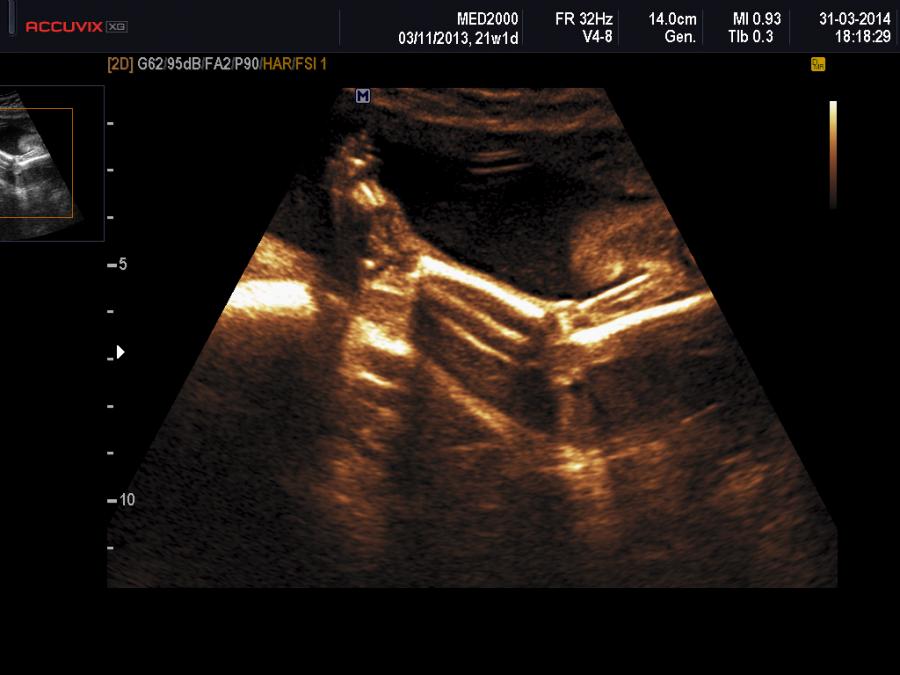

La diagnosi prenatale può essere sospettata se presenti alcune anomalie muscolo-scheletriche: ginocchio recurvato congenito, micrognazia, dislocazione del radio, piede torto, spondilolisi, spondilolistesi.